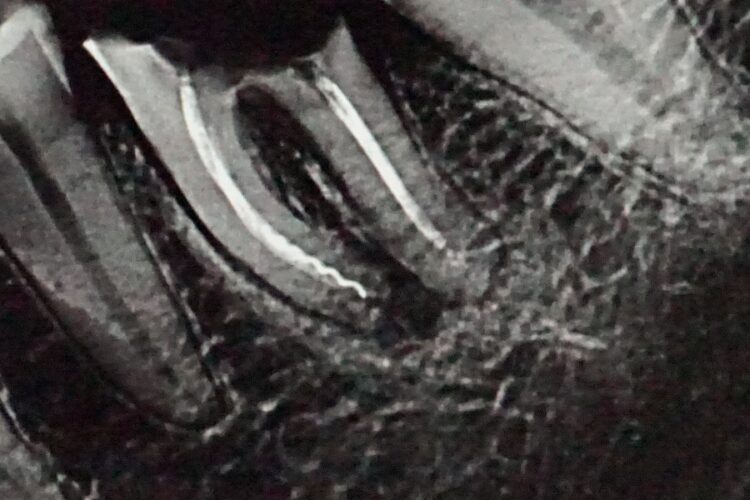

При огляді в порожнині рота між коренями нижнього шостого зуба добре видно тріщину. Для уточнення ми провели рентгенологічне дослідження, що підтвердило порушення цілісності коренів зуба. Зуб не підлягав відновленню коронкою. Пацієнтці рекомендовано видалення з одномоментною імплантацією.

Рентген імпланту через 2 місяці. Навколо імпланта вже сформовані кісткові структури, процес остеоінтеграції протікає добре.